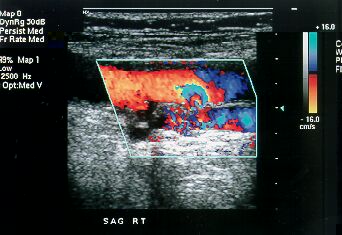

Color Doppler

What

is Color Doppler?

Color Doppler is a special ultrasound technique, which allows us to evaluate

blood vessels.

What is the principle?

Using the Doppler principle of changing pitch with velocity, ultrasound waves

that reflect from the red blood corpuscles in arteries and veins are evaluated

for velocity and amplitude and color maps of the vessels can be generated.

Is special equipment required?

An ultrasound machine equipped with color Doppler facilities is required. These

are now readily available at many centers.

What is its utility?

Color Doppler is very useful in evaluating the carotid arteries in the neck, the

heart (echocardiography), the arteries and veins in the abdomen and the arteries

and veins in the upper and lower limbs.